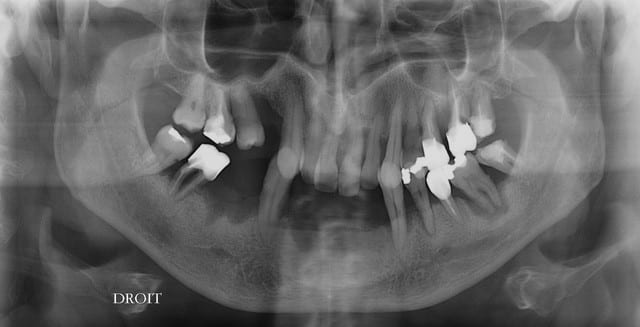

Autre cas qui peut poser un problème similaire .

Nouvelle patiente vu en urg pour resceller son bridge 22 24.

22 et 24 total recariées, tres mobiles.

> je dirai que seulement

> 2/3 dents semblaient conservables 26 et 23 et la Pm intercalée.

On sait maintenant que 2 ou 3 dents sont peut être conservables.

On n'a plus qu'à connaître l'état des dents mandibulaires, et on pourra encore aller plus loin.

2-3 dents conservables c'est une info de merde. Ce que je vois sur la photo, je suis sûr qu'on pourrait en récupérer provisoirement certaines, et c'est sûr qu'elles durent le temps de réfléchir un peu.

Pj pano haut et bas.